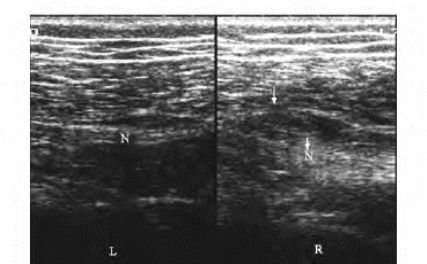

1.39.7七、其他骨、关节、肌腱、周围神经及软组织疾病